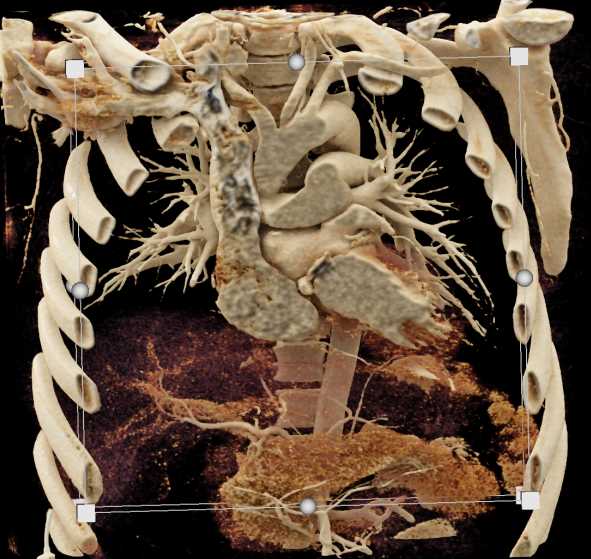

Aortic Valve Repair